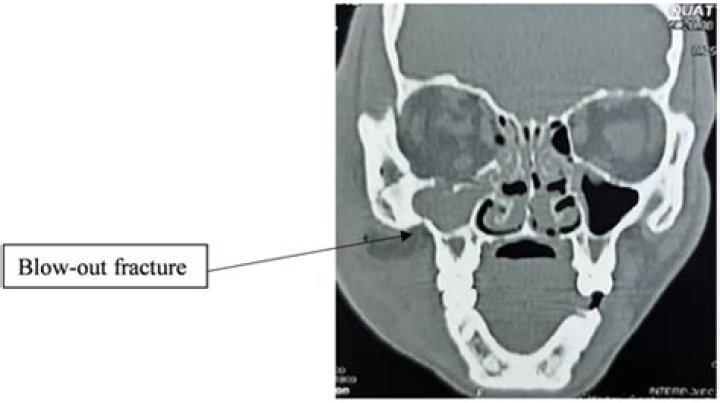

An orbital fracture occurs when one or more of the bones around the eyeball break, often caused by a hard blow to the face. To diagnose a fracture, ophthalmologists examine the eye and surrounding area. X-ray and computed tomography scans may also be taken.

Clinical diagnosis Patients who have diplopia and/or pain with vertical movements of the eyes after blunt midfacial trauma should be suspected to have an orbital floor fracture. However, the diagnosis of an orbital floor fracture without entrapment can only be made radiologically.